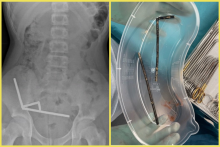

FOTO 13-ročný chlapec prehltol takmer 200 magnetov. Lekári mu museli odstrániť časť čreva SOCIÁLNE SIETE